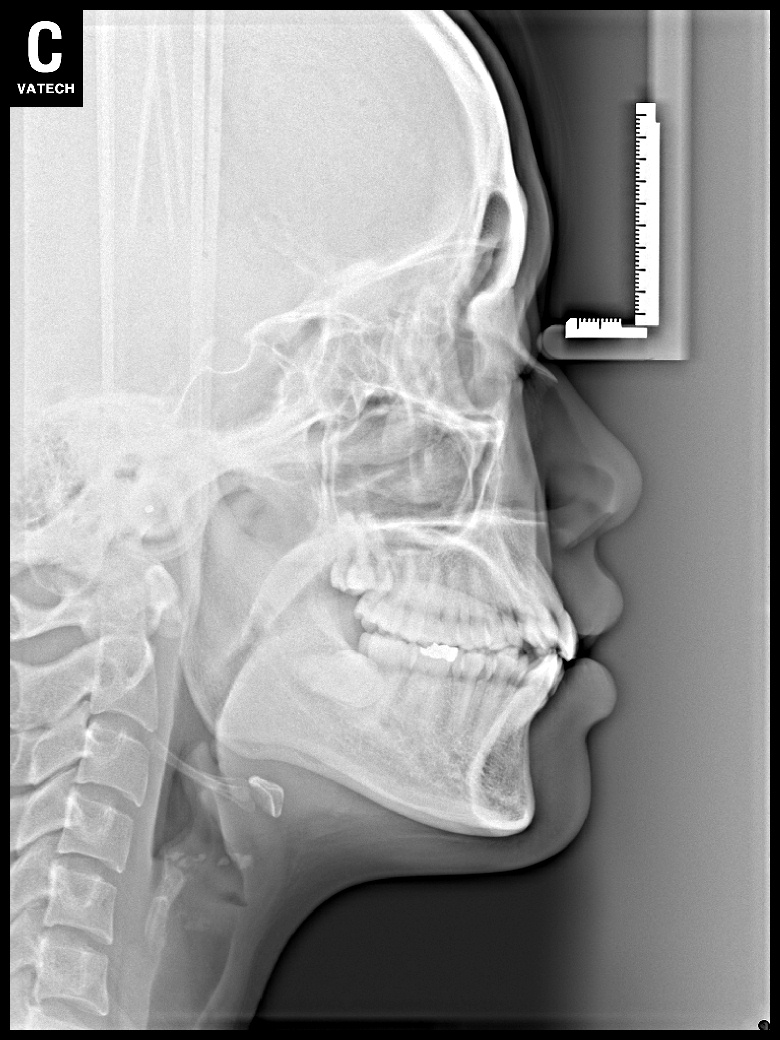

치료 전 사진입니다.